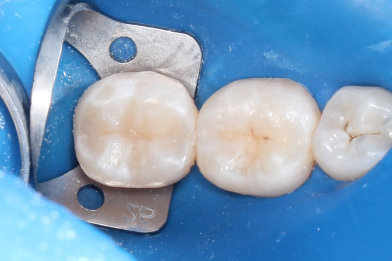

Жалобы на застревание пищи между зубами 26,25, реакция на сладкое и

Колиш Максим Петрович

холодное.

При осмотре обнаружен контактный кариес на зубах 26,25.

Лечений в один визит , восстановление функциональности композитной

реставрацией. -